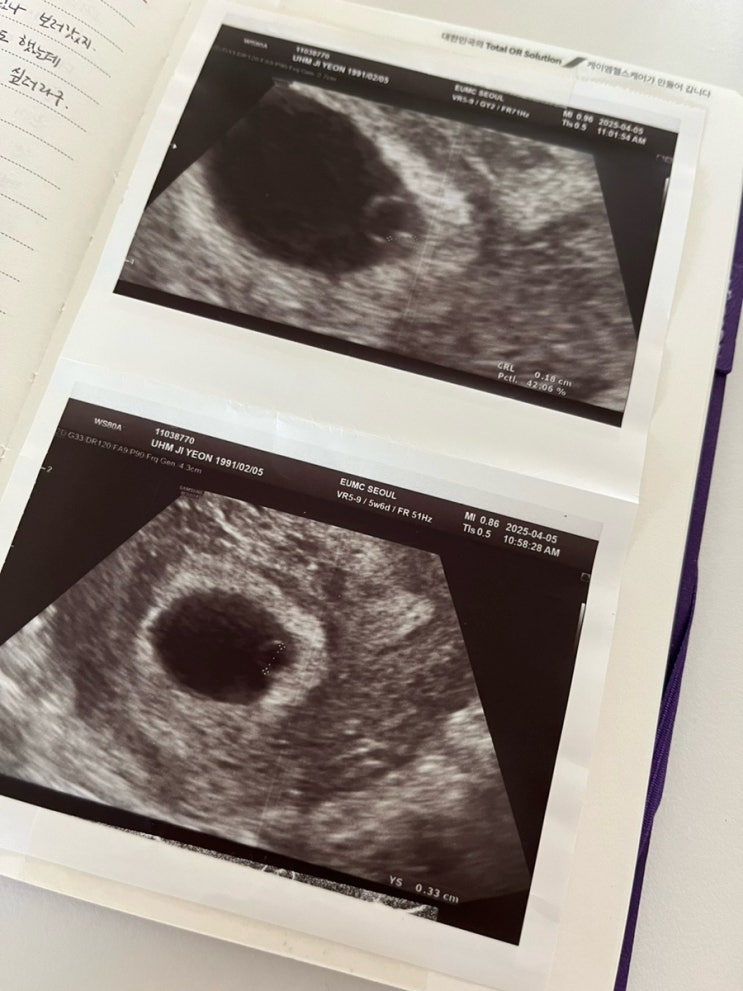

쏘울이 한테 들려주는 태교일기 - 난황 확인 그리고 일본 여행 취소..

2025년 4월 5일 토요일 일주일 만에 다시 초음파 보러 외래 방문! 이번엔 이경아 교수님 외래로 갔단다. 지...